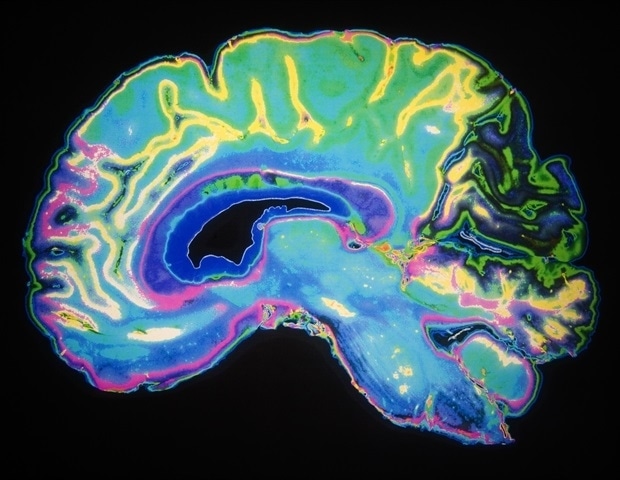

Νέα τεχνική ξεπερνά τεχνολογικό φράγμα στην τρισδιάστατη απεικόνιση του εγκεφάλου

Επιστήμονες από το Swiss Light Source (SLS) πέτυχαν μια σημαντική ανακάλυψη, χαρτογραφώντας ένα κομμάτι εγκεφαλικού ιστού σε τρισδιάστατη μορφή με απαράμιλλη ανάλυση, χρησιμοποιώντας ακτίνες Χ. Αυτή η πρόοδος ξεπερνά ένα μακροχρόνιο τεχνολογικό εμπόδιο που είχε περιορίσει τη χρήση των ακτίνων Χ σε τέτοιες μελέτες.

Με την ολοκλήρωση της αναβάθμισης του SLS, ανοίγει ο δρόμος για την απεικόνιση πολύ μεγαλύτερων δειγμάτων εγκεφαλικού ιστού με υψηλή ανάλυση, προσφέροντας νέες δυνατότητες κατανόησης της πολύπλοκης αρχιτεκτονικής του. Η μελέτη, που είναι αποτέλεσμα συνεργασίας μεταξύ του PSI και του Francis Crick Institute του Ηνωμένου Βασιλείου, δημοσιεύθηκε στο περιοδικό Nature Methods.

Ο εγκέφαλος θεωρείται ένα από τα πιο περίπλοκα βιολογικά συστήματα που υπάρχουν. Όπως εξηγεί ο Adrian Wanner, επικεφαλής της Ομάδας Έρευνας Δομικής Νευροβιολογίας στο Paul Scherrer Institute (PSI), η κατανόηση του τρόπου με τον οποίο οι νευρώνες συνδέονται μεταξύ τους είναι το κλειδί για την ανακάλυψη νέων γνώσεων στον τομέα της συνδετομικής.

«Σκεφτείτε το ήπαρ: γνωρίζουμε περίπου 40 τύπους κυττάρων, πώς είναι οργανωμένα και ποιες είναι οι λειτουργίες τους. Αυτό δεν ισχύει για τον εγκέφαλο», επισημαίνει ο Wanner. «Η διαφορά δεν είναι στα κύτταρα, αλλά στο πώς είναι οργανωμένα και συνδεδεμένα». Στο ένα κυβικό χιλιοστό εγκεφαλικού ιστού υπάρχουν περίπου 100.000 νευρώνες, συνδεδεμένοι μέσω 700 εκατομμυρίων συνάψεων και 4 χιλιομέτρων ‘καλωδίων’.

Η σύνδεση αυτών των νευρώνων μέσω των συνάψεων καθορίζει τη λειτουργία του εγκεφάλου και σχετίζεται με ασθένειες όπως η νόσος Αλτσχάιμερ. Ωστόσο, η πολυπλοκότητα αυτής της καλωδίωσης σε τρεις διαστάσεις είναι εξαιρετικά δύσκολο να μελετηθεί. «Αν πάρουμε ένα νευρωνικό δίκτυο με 17 νευρώνες, υπάρχουν περισσότερες δυνατότητες σύνδεσής τους απ’ ότι άτομα στο σύμπαν», λέει ο Wanner. «Δεν μπορούμε απλώς να το μοντελοποιήσουμε. Πρέπει να το μετρήσουμε».

Η τρέχουσα μέθοδος απεικόνισης για αυτόν τον τύπο μελέτης είναι η ηλεκτρονική μικροσκοπία όγκου. Αυτή η διαδικασία απαιτεί την κοπή κυβικών χιλιοστών εγκεφαλικού ιστού σε δεκάδες χιλιάδες υπερλεπτές τομές, οι οποίες στη συνέχεια απεικονίζονται και ανασυντίθενται υπολογιστικά, μια διαδικασία που είναι επιρρεπής σε σφάλματα και οδηγεί σε απώλεια πληροφοριών.

Η λύση βρίσκεται στις ακτίνες Χ, οι οποίες μπορούν να διεισδύσουν σε χιλιοστά ή και εκατοστά, επιτρέποντας την απεικόνιση μεγαλύτερων κομματιών εγκεφαλικού ιστού χωρίς την ανάγκη κοπής. Στην ακτινοβολία cSAXS του SLS, οι ακτίνες Χ υψηλής φωτεινότητας έχουν επιτρέψει την απεικόνιση τσιπ υπολογιστών με ανάλυση μόλις 4 νανομέτρων – ένα παγκόσμιο ρεκόρ.

Ωστόσο, για τα βιολογικά ιστούς, το πρόβλημα είναι η αντίθεση. Οι επιστήμονες χρησιμοποιούν βαφές με βαρέα μέταλλα για να αυξήσουν την αντίθεση, αλλά αυτό έχει ως αποτέλεσμα την απορρόφηση των ακτίνων Χ, προκαλώντας παραμορφώσεις στα δείγματα. Η νέα προσέγγιση που ανέπτυξαν ο Wanner και οι συνεργάτες του περιλαμβάνει μια εποξειδική ρητίνη που μπορεί να διεισδύσει στα βιολογικά ιστούς, προσφέροντας μια ελπιδοφόρα λύση σε αυτό το πρόβλημα.